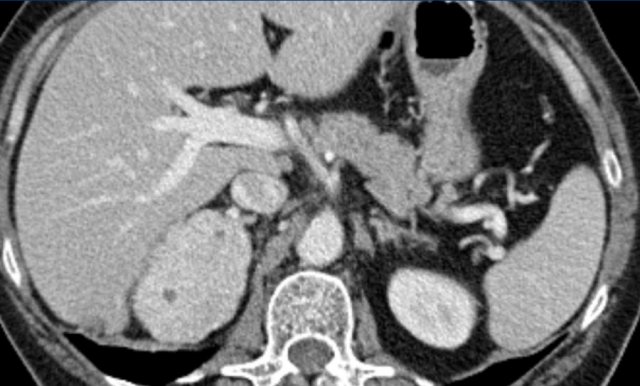

The images show bilateral adrenal incidentalomas found in a 64-year old patient scanned for analysis of an abdominal aneurysm.

The scan in the arterial phase shows bilateral lesions with a density of 50 HU.

On the non-enhanced CT performed a few days later, the density in both adrenal glands was less than 10 HU, proving these to be lipid-rich adenomas.